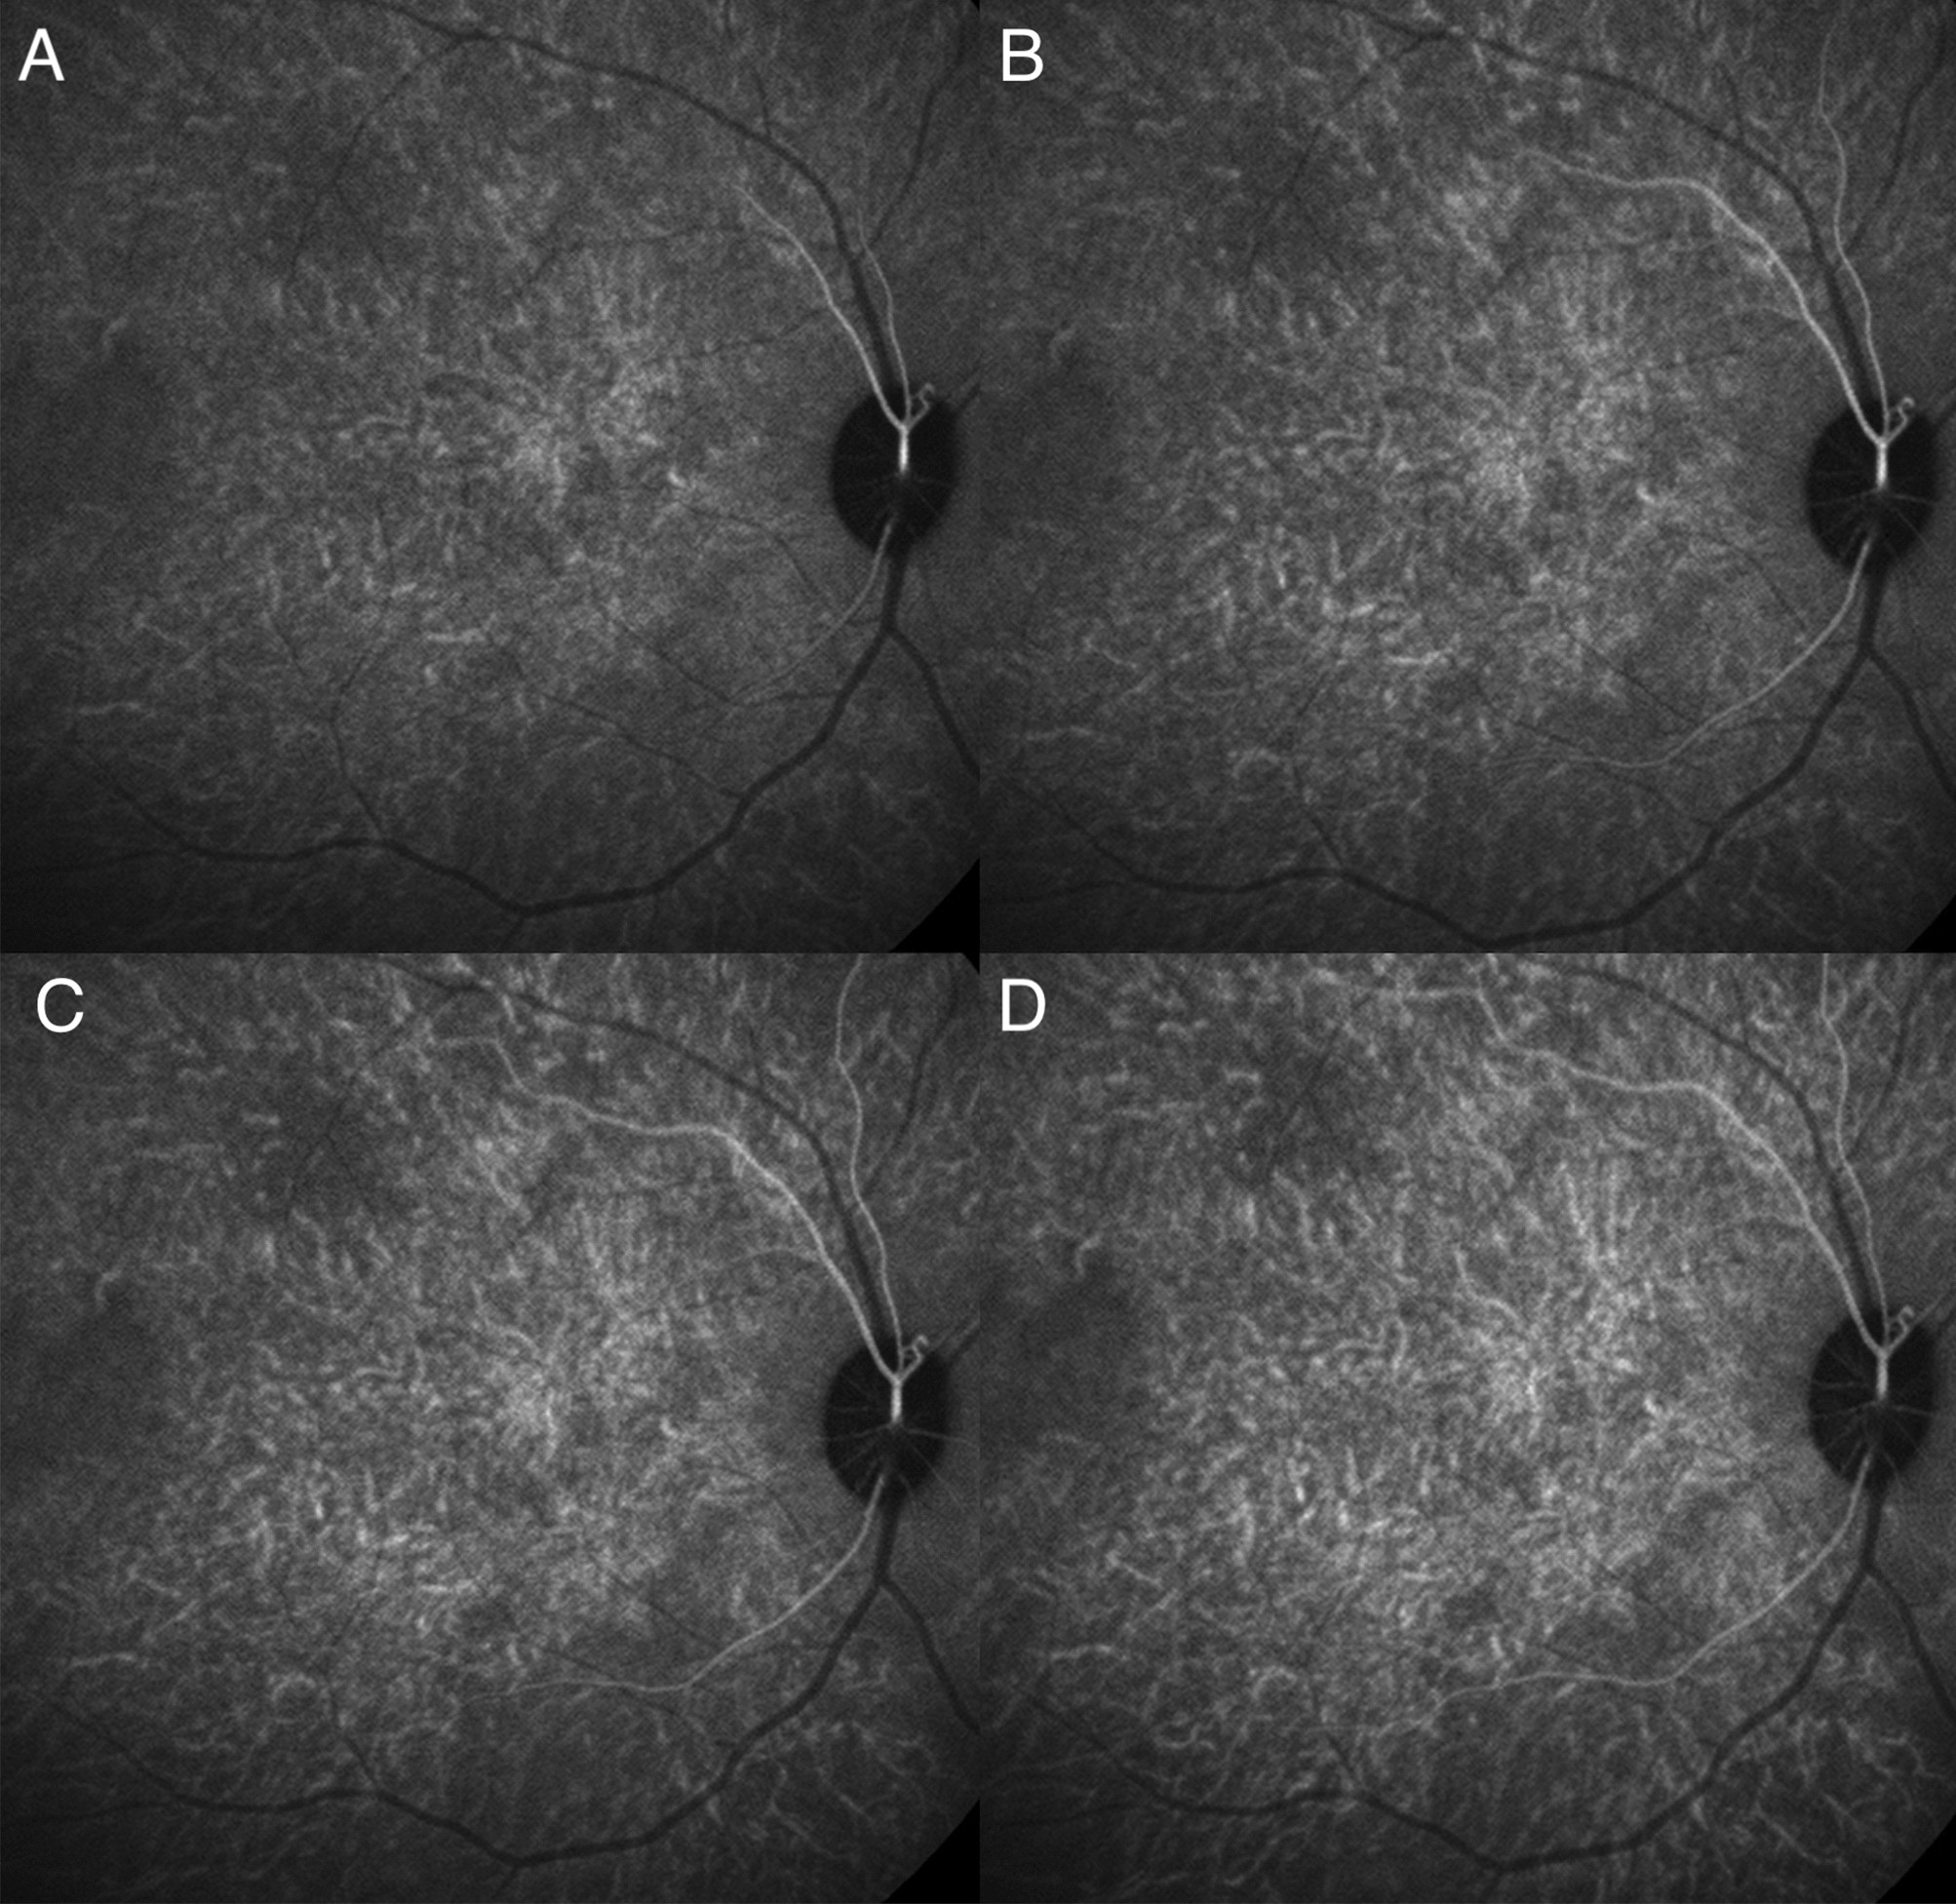

Figure 1

Indocyanine green angiography without subtraction. (A–D) showed consecutive frames from video angiography. Each frame was 22/100 s apart. Dye first appeared in vessels in the peripapillary and macular area and progressed laterally along individual vessels.